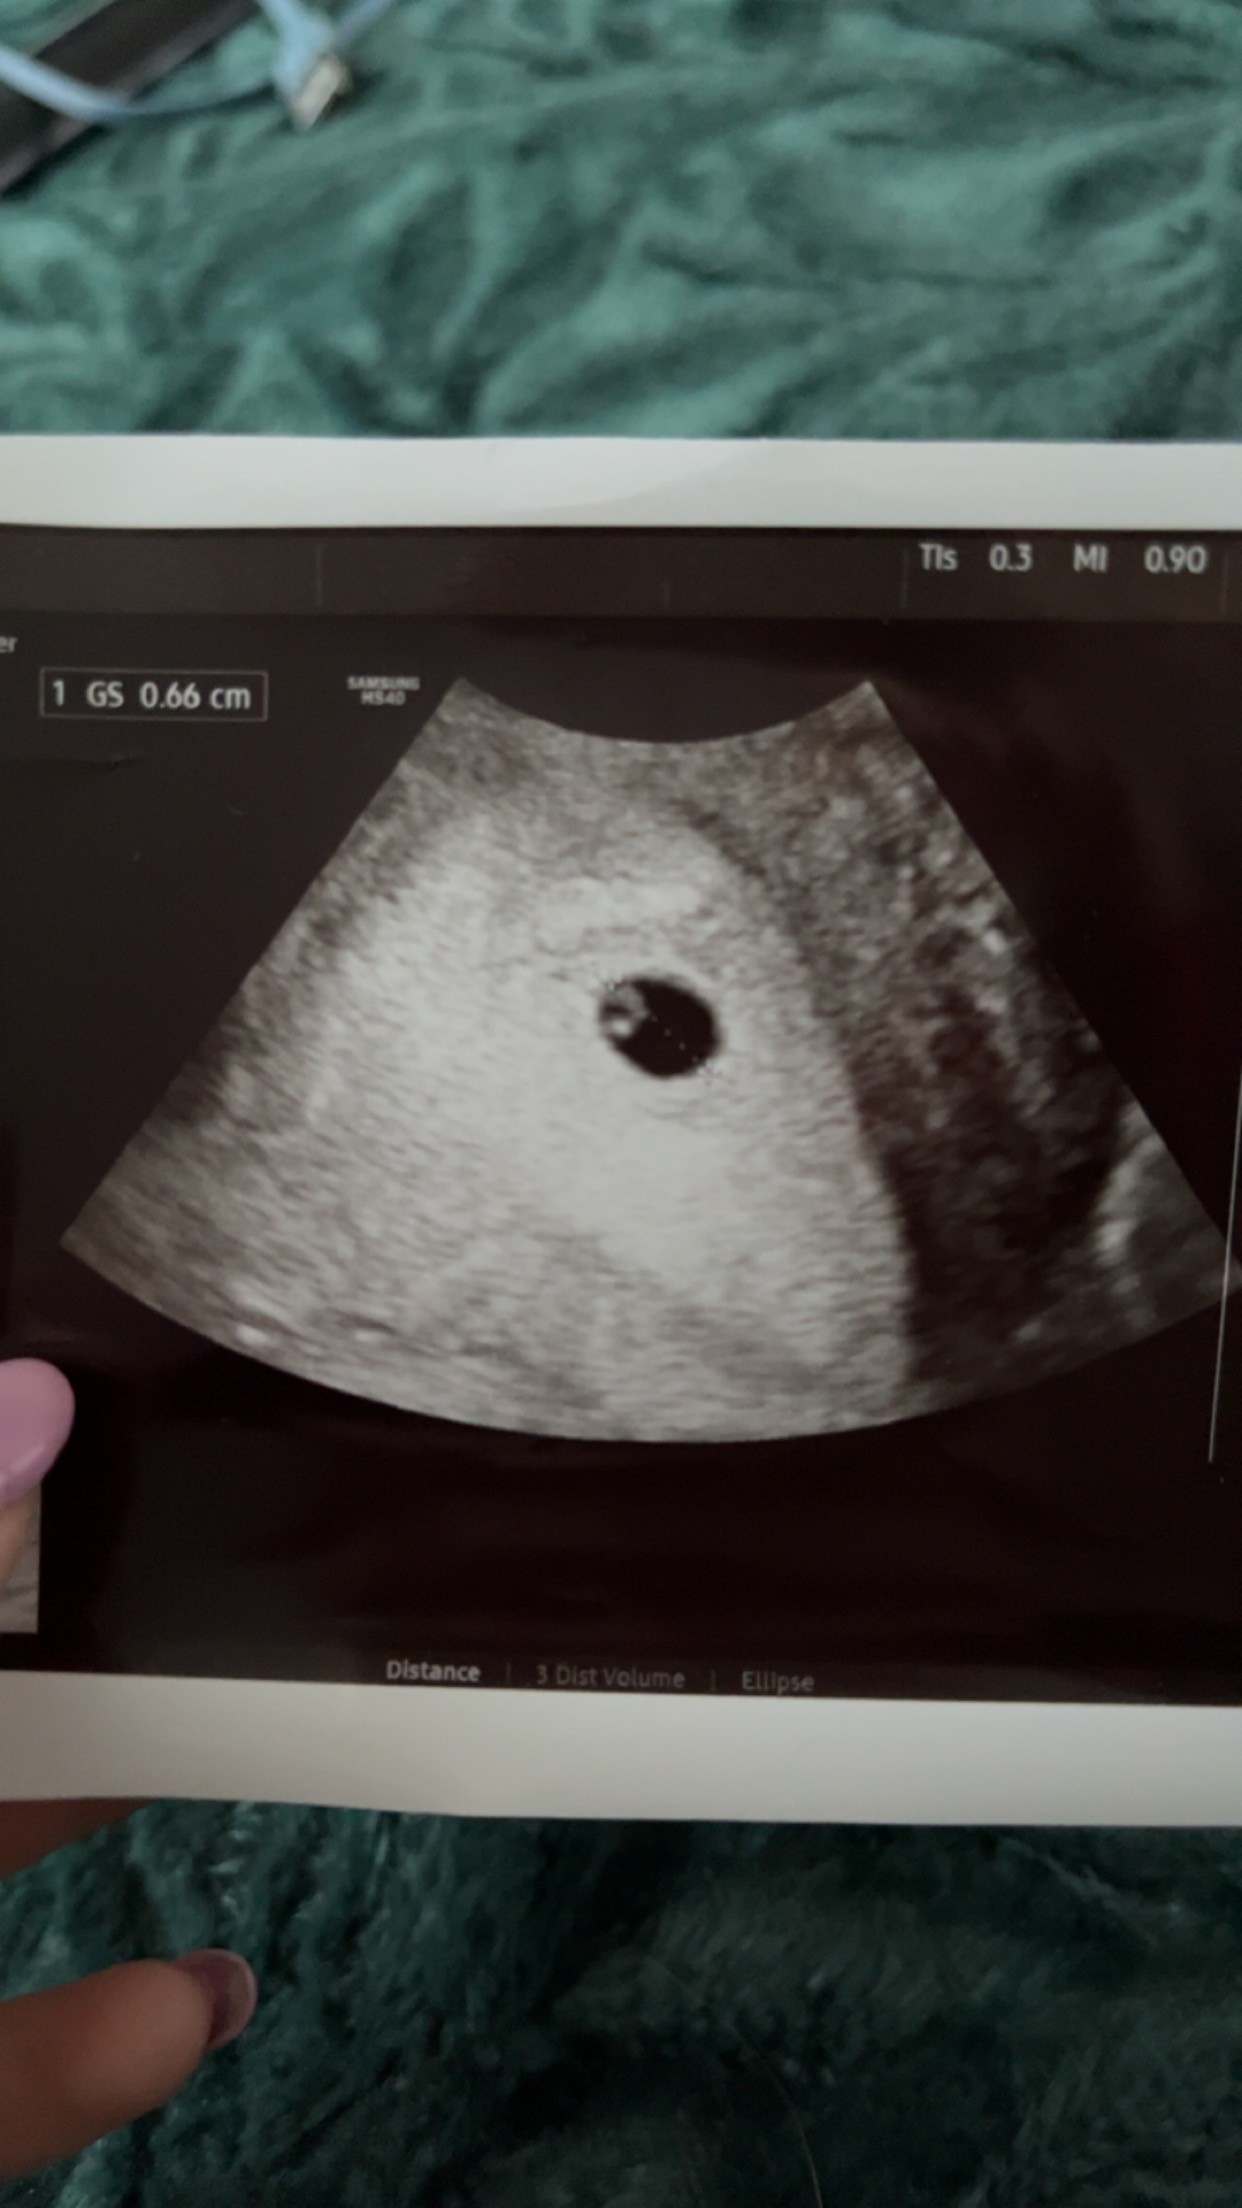

Ja Już po moim pierwszym USG miałam iść 9 ale nie wytrzymałam.. z okresu wynika ze to jest 6 tydzień ale ciąża delikatnie młodsza 😅 Moja ginekolog powiedziała ze jest pięknie❤️ Kolejna wizyta 23.05

Załączniki

• B66BF383-A862-436B-9D92-49A5022957F3.jpeg

B66BF383-A862-436B-9D92-49A5022957F3.jpeg

263,8 KB · Wyświetleń: 172